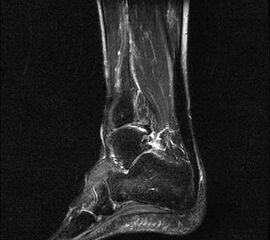

Stoßwellentherapie bei osteochondralen Läsionen

Die Osteochondrosis dissecans tali (OD) ist definiert als lokalisierte Pathologie der Gelenkfläche des Talus, die zur Abtrennung eines kartilaginären Fragmentes und subchondralen Knochens führen kann 93. Es existieren am Körper 3 Prädilektionsstellen für die Entwicklung einer OD mit unterschiedlicher Häufigkeit: Femurkondylen 75%, Talus 12% und Capitulum humeri 12%, sowie sonstigen Lokalisationen 1%. Abhängig vom Zeitpunkt des Auftretens unterscheidet man die juvenile Form (offene Wachstumsfuge) von der adulten Form (geschlossene Wachstumsfuge) (Dotti 2002).

Nach Dotti sind am Talus vorrangig die posteromediale und die anterolaterale Talusschulter betroffen. Die Ätiologie der OD an der anterolateralen Talusschulter scheint vermehrt traumatisch/repetitiv mikrotraumatisch zu sein, die der posteromedialen Talusschulter vermehrt idiopathisch.

Die Stadieneinteilung nach Berndt und Harty umfasst 4 Stadien und ist unabhängig von der Lokalisation der OD anwendbar 94.

Die Stadieneinteilung nach ARCO (Association Internationale de Recherche sur la Circulation Osseuse) berücksichtigt die Kombination aus MRI-Zeichen, Nativradiologie und Knochenszintigraphie 95.

Die Therapie orientiert sich an der Stadieneinteilung und Lokalisation der OD, sowie am Lebensalter des Patienten. Eine aktuelle Metaanalyse zur OD am Talus 96 zeigt ein Durchschnittsalter von 28 Jahren, bei jüngeren Patienten ist ein günstigerer Verlauf zu erwarten. Die höchste Rate an Spontanheilungen wird bei Kindern beobachtet.

Als Alternative zu operativen Maßnahmen wird bei frühen Stadien der OD auch der Einsatz fokussierter Stoßwellentherapie diskutiert, wenngleich es bislang wenig klinische Studien zur ESWT bei OD am Talus gibt.

Die ESWT wird in der Regel in einer Sitzung unter Leitungs– oder Allgemeinanästhesie durchgeführt, wobei nach Empfehlungen der DIGEST eine mittlere Energieflussdichte von 0,35mJ/mm² und eine Anzahl von 2500 Impulsen empfohlen wird. Bei hochenergetischer Behandlung (>0,5mJ/mm²) kann eine Schädigung des Knorpels nicht sicher ausgeschlossen werden 97.

Nach der Behandlung wird eine Entlastung für ca. 2 - 6 Wochen empfohlen. MRT-Kontrollen sind nach 3, 6 und 12 Monaten sinnvoll.

Aufgrund der Datenlage kann die Anwendung der ESWT bei osteochondralen Läsionen des Talus in frühen Stadien (1 und 2 nach ARCO) erwogen werden. Für eine Therapieempfehlung sind allerdings weitere Studien, insbesondere zur Therapie der OD des Talus zwingend erforderlich. Aufgrund der technischen Schwierigkeit der Behandlung bei teilweise schlechter Erreichbarkeit der Läsion, sollte diese Indikation erfahrenen Anwendern vorbehalten bleiben.